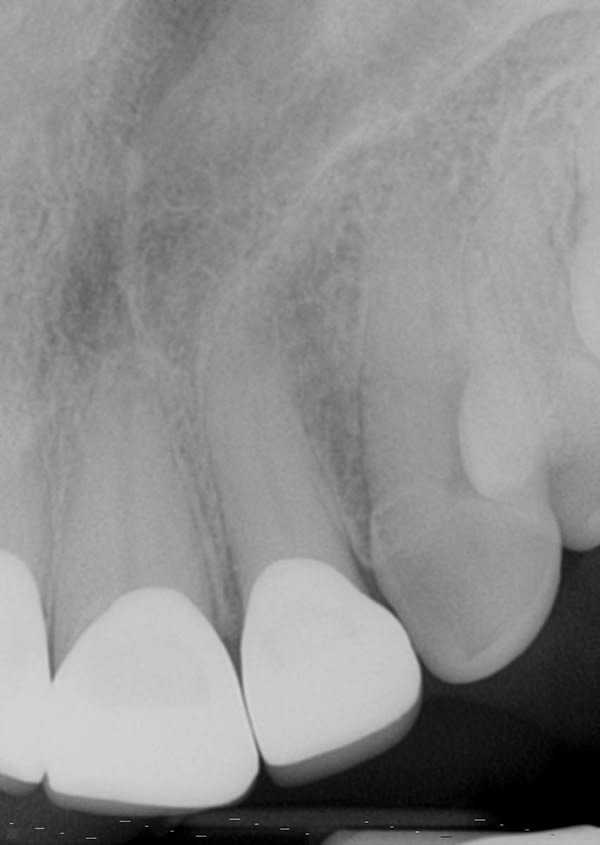

A female patient aged 57 years presented with altered passive eruption of the maxillary anterior teeth, which was diagnosed as a secondary condition to tooth erosion resulting from long-standing gastroesophageal reflux disease (GERD). Clear aligner therapy was initiated to level and align the occlusion and intrude the maxillary anterior teeth back to their original gingival position. After 18 months of poor patient compliance, improvement in tooth position was minimal and the amount of clinical overjet that was desired was not achieved. This limited the restorative armamentarium, and a decision was made to proceed with monolithic zirconia-oxide restorations. Following teeth preparation and tissue retraction, the case was impressed using an intraoral scanner (iTero® Element 2, Align Technology, Inc., itero.com). The final restorations were made of zirconium dioxide with a feldspar veneering ceramic shade 1M1 as the pressed layer on porcelain on the facials. The outcome of the case met the patient's primary concerns, achieving the lengthening and lightening of the anterior teeth that she desired. Because of the patient's continued challenges with GERD, however, she reported having difficulty with compliance related to the clear aligner therapy and whitening protocols, precluding a more ideal result. Nonetheless, the patient was pleased with her new smile and the clinician, given the challenging circumstances, was satisfied with the clinical results of the final restorations.